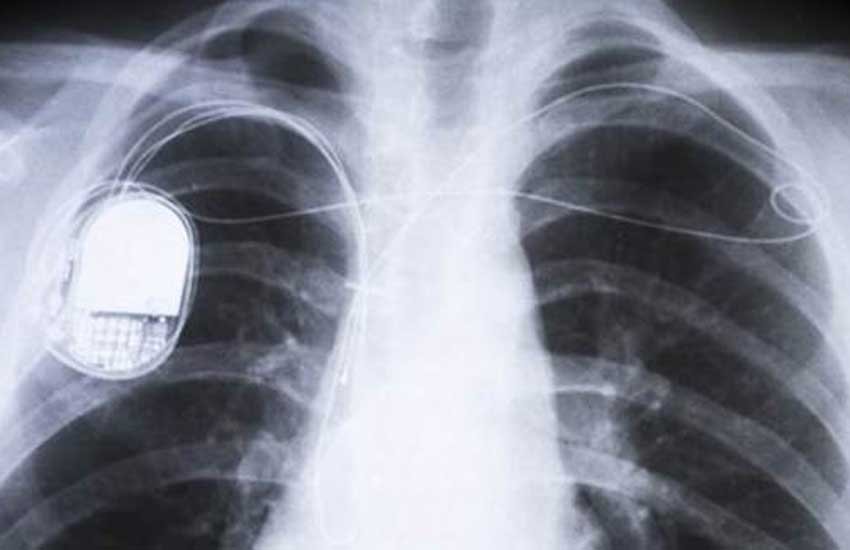

जेब घड़ी के आकार वाले पेसमेकरों को छाती पर चीरा लगा कर त्वचा के नीचे लगाया जाता है। लीड कहलाने वाली तारें इस उपकरण को दिल से जोड़ती हैं और विद्युत सिग्नल भेजती हैं। इससे दिल की गतिविधियां नियंत्रित रखी जाती हैं। नए बिना तार वाले उपकरण में लीड की जरूरत नहीं होती क्योंकि यह दिल के अंदर होता है। यह इसके खराब हो जाने की संभावना भी खत्म करता है। लेकिन यह उपकरण अब भी चलता बैटरी से ही है। इस बैटरी को अक्सर उन्हीं बैटरियों की तरह बदलना पड़ता है, जिनका इस्तेमाल पारंपरिक पेसमेकरों में होता है।